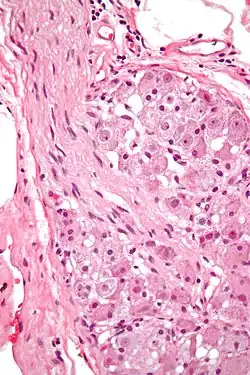

En neurofisiología, una célula ganglionar es una célula que se encuentra en un ganglio (un grupo de neuronas en el sistema nervioso periférico). Ejemplos de células ganglionares incluyen:

- Célula ganglionar de la retina (CGR) que se encuentra en la capa de células ganglionares de la retina [1]